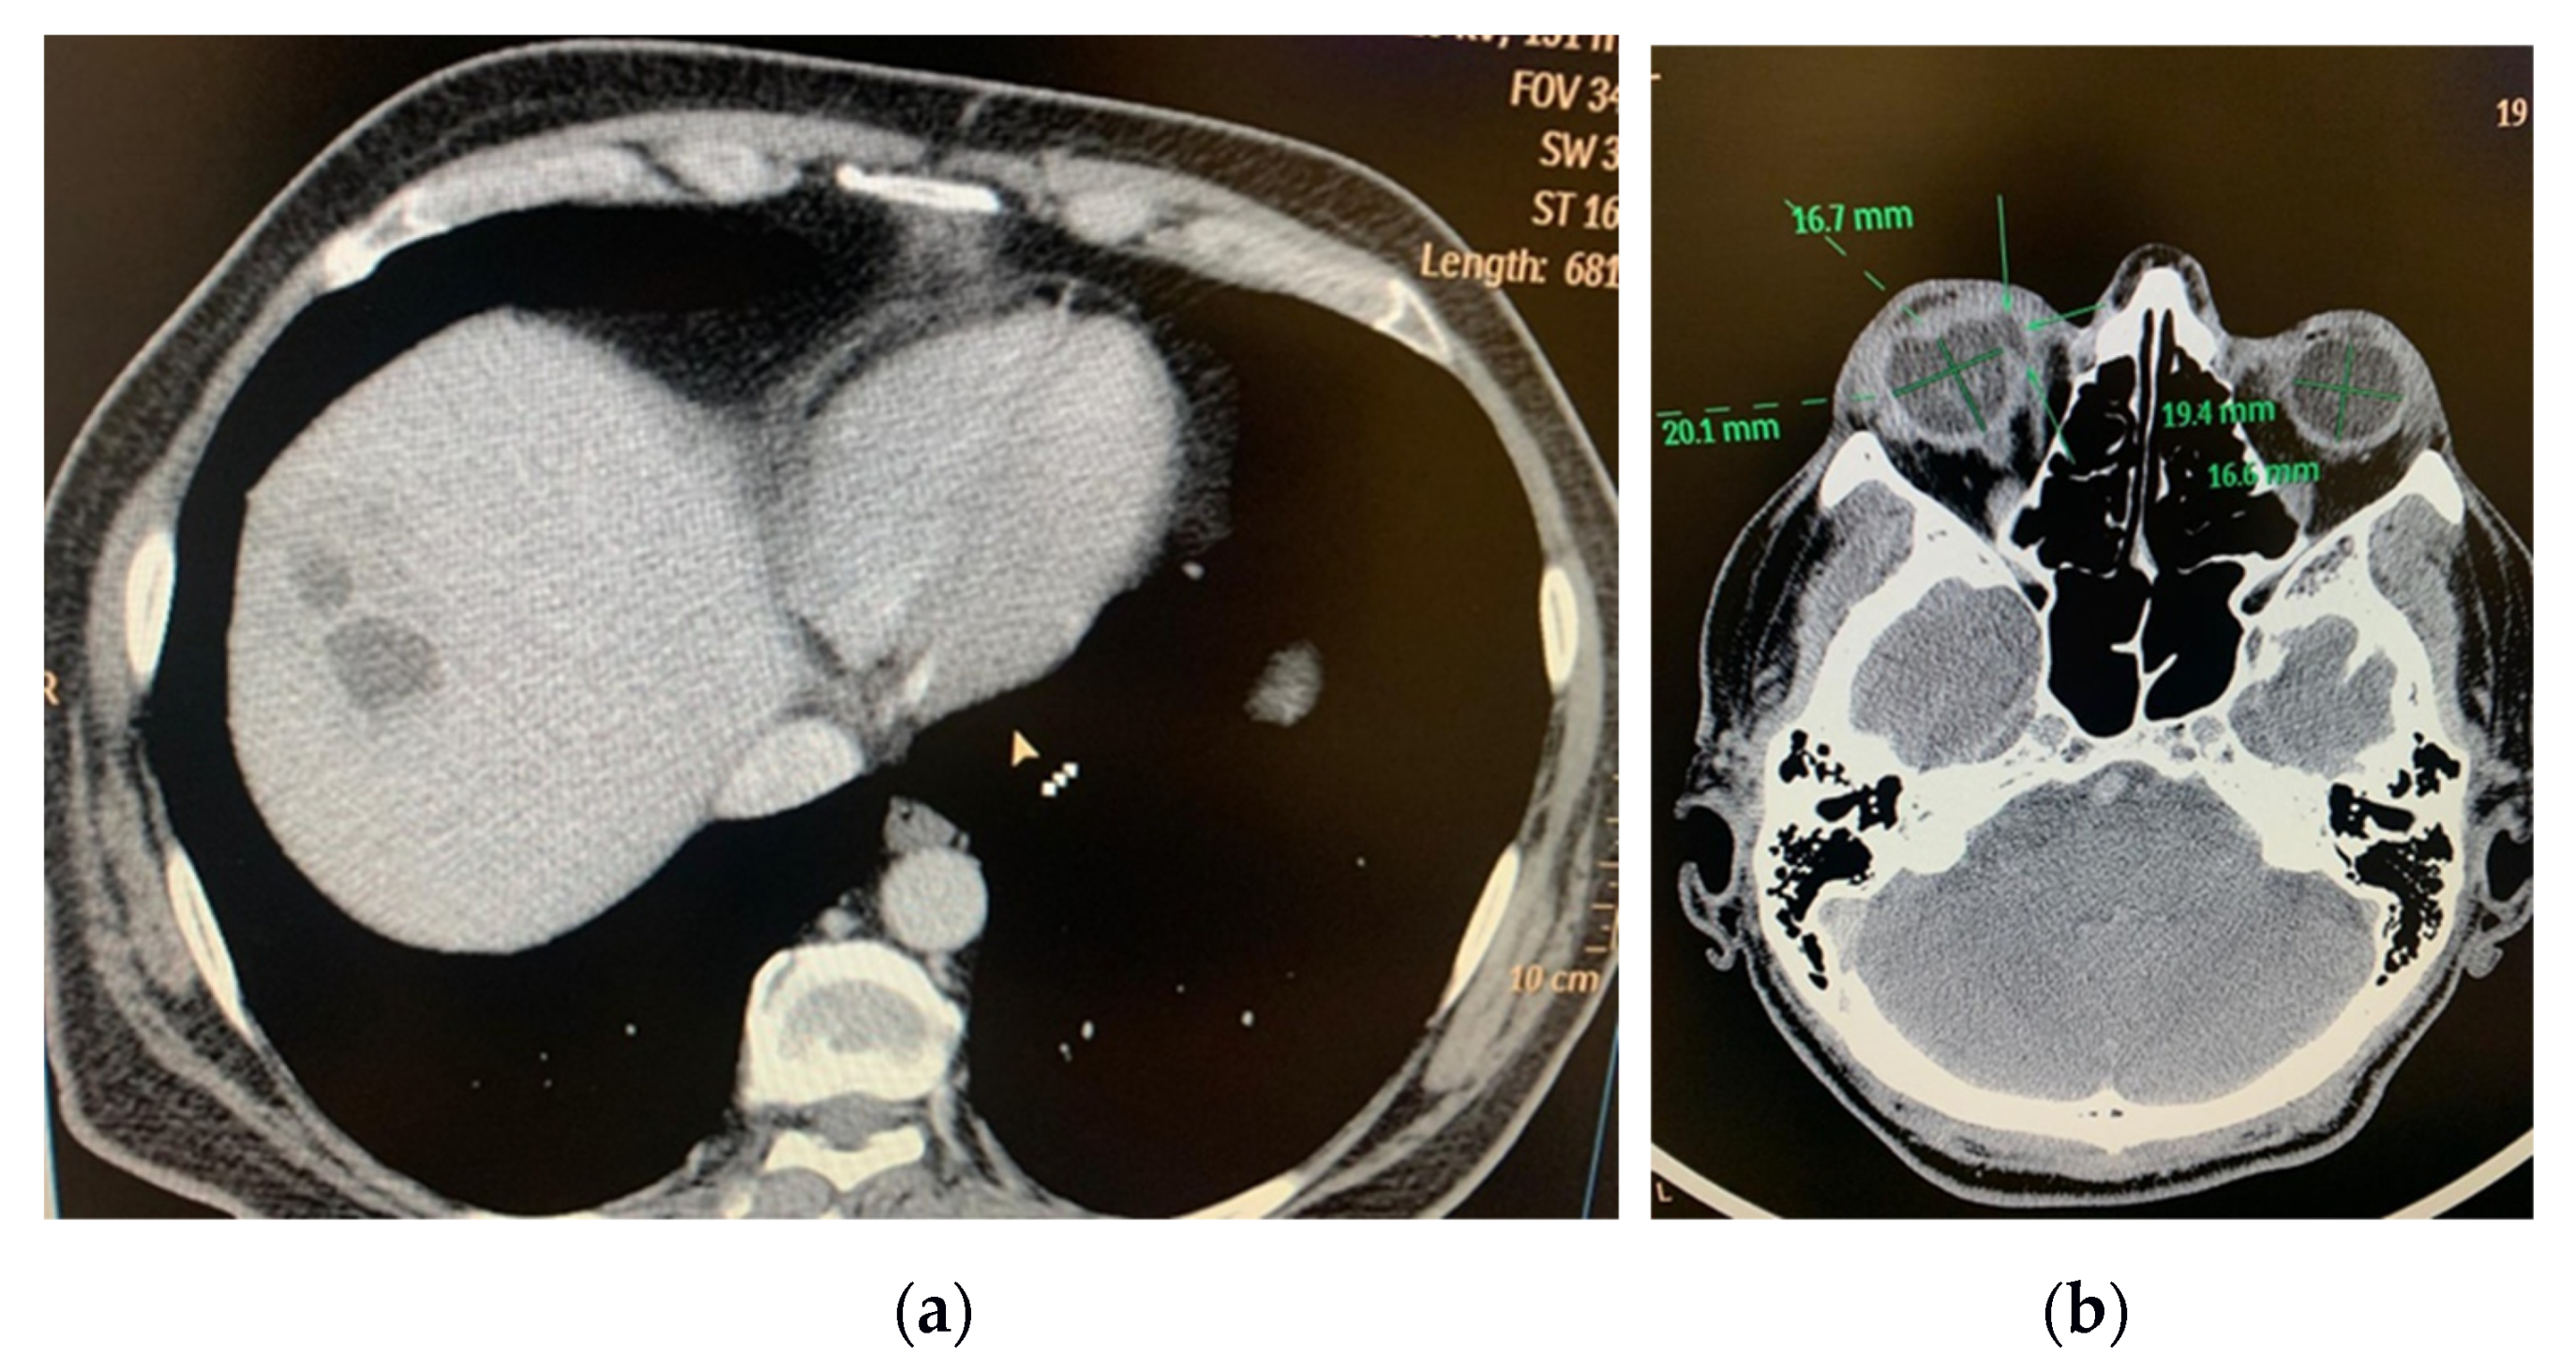

4.2. Imagistic and Laboratory Tests